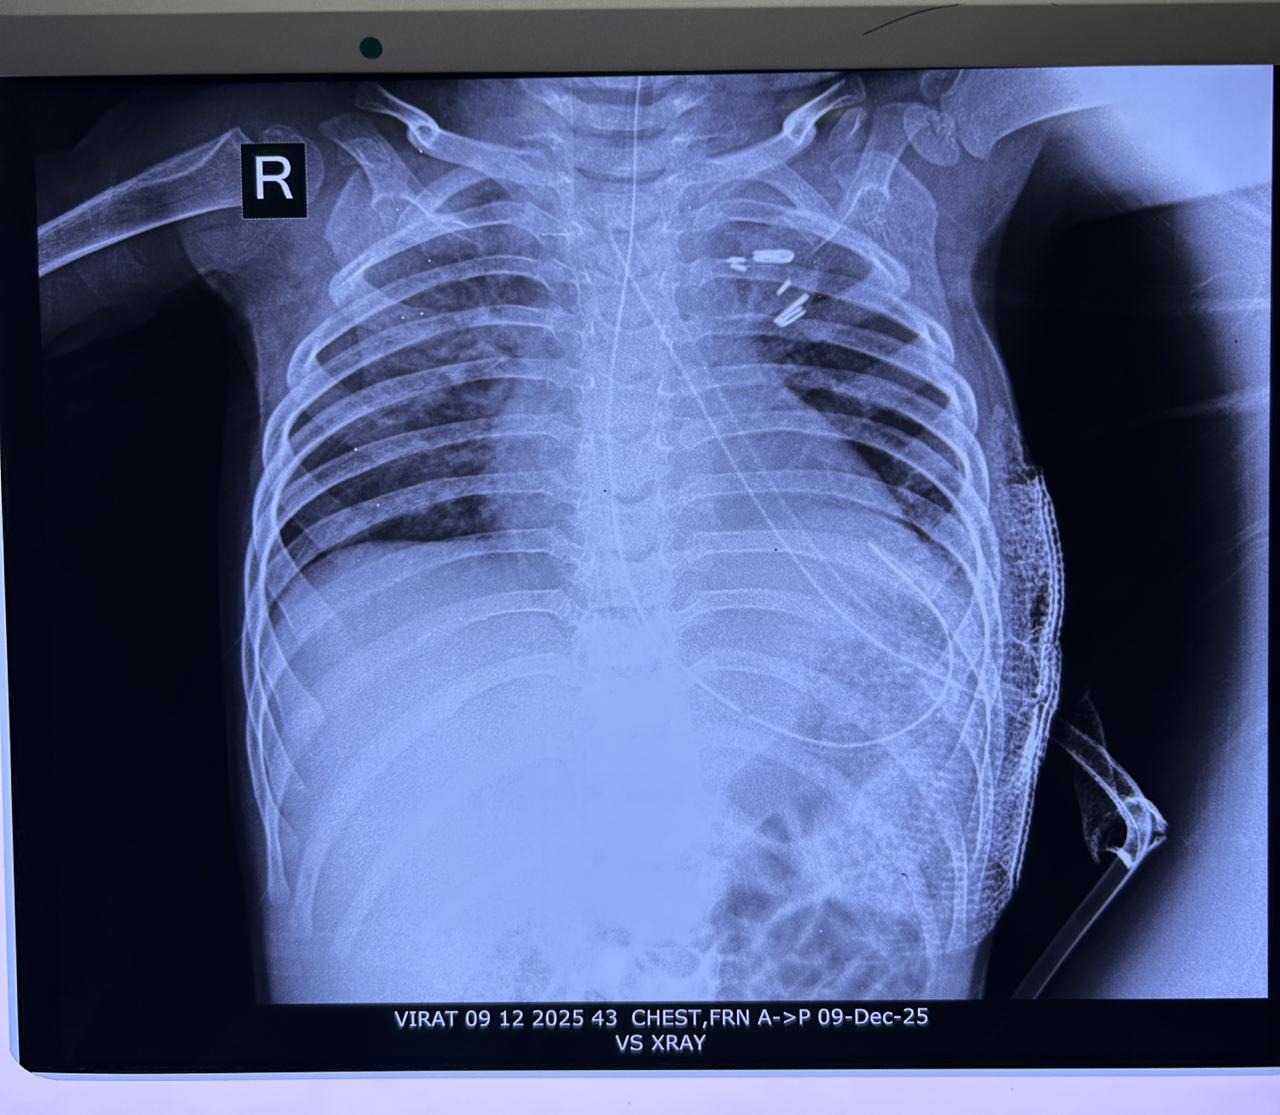

डॉ रावत ने बताया कि 21 नवंबर को मरीज को पीडियाट्रिक सर्जरी विभाग में भर्ती किया गया और तुरंत इलाज शुरू किया गया। मरीज के X-Ray & MRI द्वारा पता लगा कि मरीज के बांए फेफड़े में पैदायशी खराबी है जिसे Lobar Emphysema कहते हैं। मरीज का ऑपरेशन बीती 3 दिसंबर को थोराकोस्कोपिक विधि (दूरबीन विधि) से किया गया, ऑपरेशन में साढ़े तीन घण्टे का समय लगा। मरीज को 2-3 दिनों तक वेंटिलेटर पर रखा गया, जिसके बाद उसे ऑक्सीजन पर रखा गया। उन्होंने बताया कि अब मरीज पूरी तरह से स्वस्थ है और उसे डिस्चार्ज किया जा रहा है। मरीज के परिजन काफी खुश हैं।